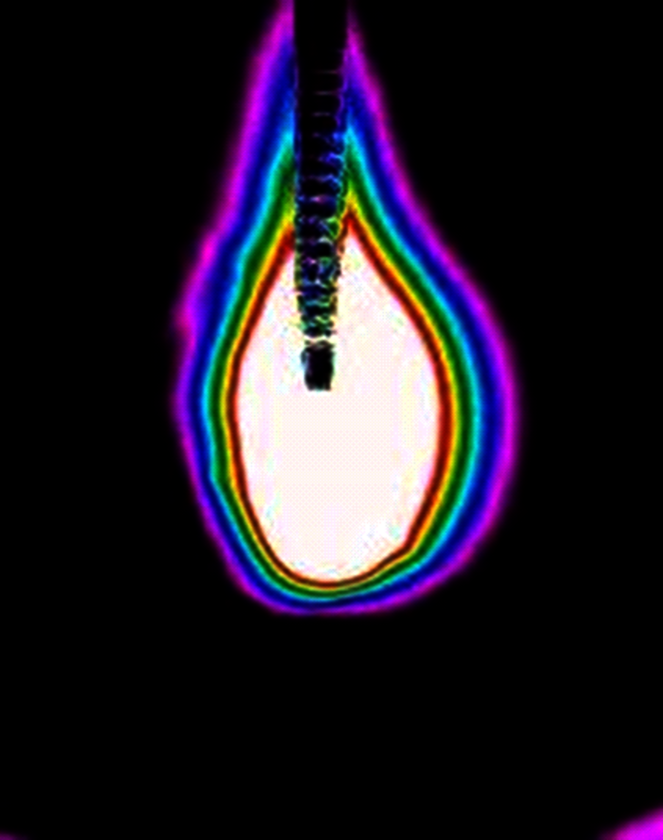

Eine besondere Spezialität liegt in der minimalinvasiven Behandlung von Wirbelmetastasen mittels Radiofrequenzablation (RFA). Mit einer RFA kann man Patienten mit spinalen Knochenmetastasen schnell und ohne großen Aufwand zu einer deutlichen Verbesserung der Lebensqualität verhelfen. Unter Radiofrequenzablation ist die Hitzezerstörung des Tumorbefalls zu verstehen (Abbildung 3). Die Daten, die zur Überprüfung des Behandlungserfolgs und der Behandlungssicherheit dieser Methode in den letzten Jahren erhoben worden sind, haben gezeigt, dass diese Eingriffe sehr sicher, hilfreich und gut verträglich sind. Daher schlagen neue, internationale Behandlungsleitlinien nun vor, eine solche Radiofrequenzablation bei schmerzhaften Wirbelsäulenmetastasen zu einer schnellen und andauernden Schmerzlinderung einzusetzen. Zumeist direkt nach dem Eingriff ist eine bessere Beweglichkeit infolge der Schmerzreduktion möglich. Wird die Radiofrequenzablation kombiniert mit der Einspritzung von Knochenzement in den befallenen Wirbel, lässt sich zudem die Stabilität der Wirbelsäule verbessern und das Risiko einer Rückenmarkschädigung durch ein Zusammenbrechen des Tumor-befallenen Wirbels reduzieren.

Abbildung 3: Hier sieht man die Zonen der Hitzeentwicklung um die Sonde. In der weißen, zentral gelegenen Zone ist die Hitzeentwicklung am größten. Die farbigen Linien beschreiben den Temperaturabfall und im Bereich der violetten Linie ist die Temperatur schon fast wieder normal.